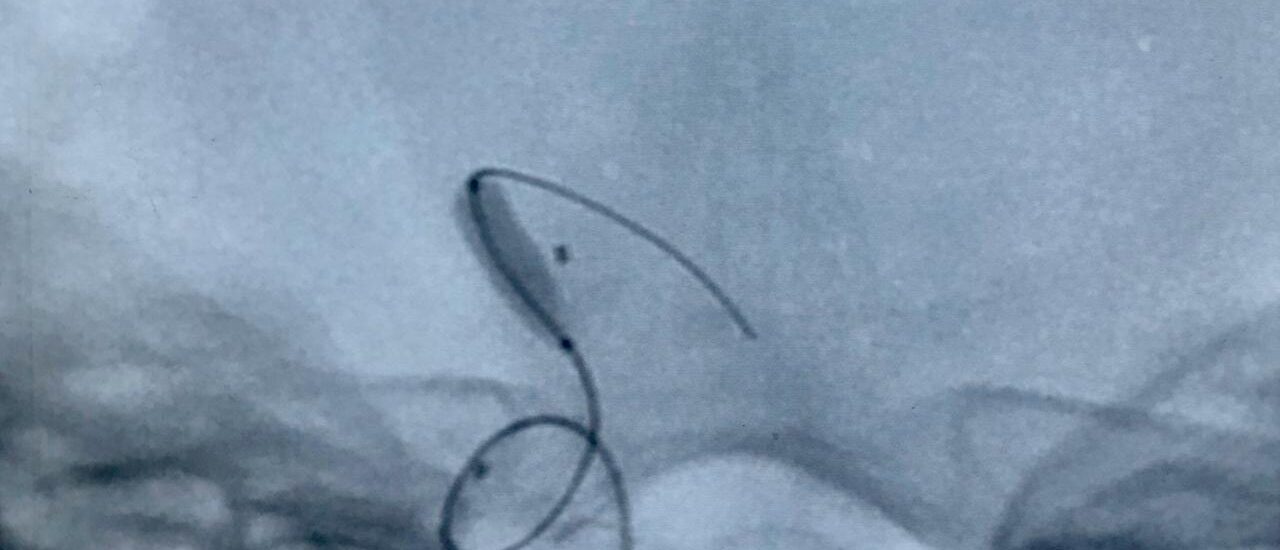

Lminectomy C3 down to C6 augmented by lateral mass fixation

Male 55 year daibetc known CSM operated 5 years by C5 C4 lamenectomy Pre operative Presented by progressive mylopathy VAS neck pain 8JOA score 9Preoperative radiologyCanal stenosis adjacent segment disease reversed cervical kyphosis. Global sagittally imbalanceOperated by extended laminectomy C3 down to C6 augmented by…